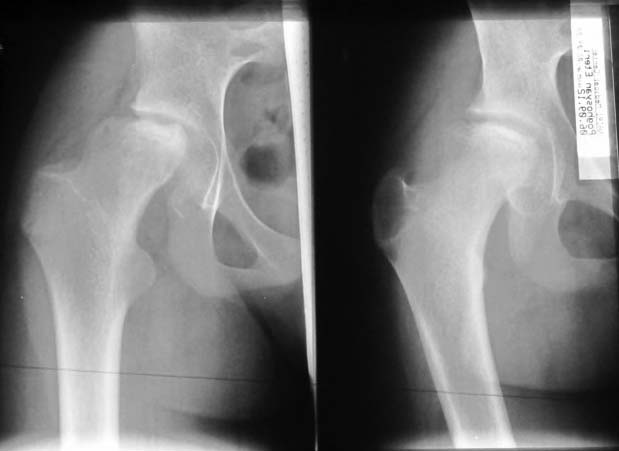

Аршак! Сделай КТ, лучше трехмерку. Дальше будем решать. Процесс по восстановлению эпифиза завершился, но с явной деформацией. АИФ

У меня более взрослые больные с последствиями и поэтому вопрос к педиатрам-специалистам по заболеванию Пертес. Не вызывает ли сомнения диагноз? Меня смущает небольшой срок истории и возраст пациентки. Болезнь может встречаться до 12 летнего возраста, но к этому времени у многих заканчиваются все стадии развития заболевания, включая вовлечение в процесс ацетабулума. Обычно процесс течение заболевания немного дольше, чем "7 месецев назад стали замечать хромоту".

Встречается ли заболевание без характерного склероза с молниеносным течением в 12 летнем возрасте? По-моему, изчезновение головки в короткий срок характерно для септических состояний, и поэтому на первое место в дифференциальной диагностике я бы поставил на септический артрит? Заново собрать анамнез на восспалительный процесс, анализы, пункция?

Доисследование покажет, что от чего, но это не сохранит головку бедра. Лечение состоит в ограничении нагрузки с периориентацией головки. От подвывиха головки сохранит варусная остеотомия, и в дальнейшем создаст опору. После операции движение в суставе на Continuous passive motion.

Классическая болезнь Легг-Кальве-Пертеса (ЛКП) проходить по пути: ишемия- асептический некроз головки- резорбция очага некроза-субхондральный перелом( проседание головки)- второй эпизод ишемии. В возрасте после 10 у девочек ( чаще активно занимающихся спортом) процесс, как правило начинается с "перегрузочного " субхондрального перелома. Лечение первый этап. Доступ: Бернский оперативный вывих бедра ( само рассечение капсулы,периоста по передней поверхности шейки произведет декомпрессию медиальной огибающей артерии, процедура: или trapdoore ( элевация хряща при его сохранности :J Pediatr Orthop. 1995 Jan-Feb;15(1):7-15."Trapdoor" procedure for osteonecrosis with segmental collapse of the femoral head in teenagers.) или остеохондральный дебридмент, резекция круглой связки.Обязательно: microfracturing, ревизия губы и ее подшивание. Второй этап через 3-4 мес в зависимости от сохранности головки или задняя ротационная остеотомия по Соколовскому ( передняя опасна из-за натяжения медиальной огибающей артерии) или вальгизирующая ( овал головки расположить горизонтально). С уважением Филипчук.

In this age prognosis is bad , but I think that she will improve after Vagus osteotomy -the goal is to remove necrotic part of the head from the weight bearing edge of the acetabulum